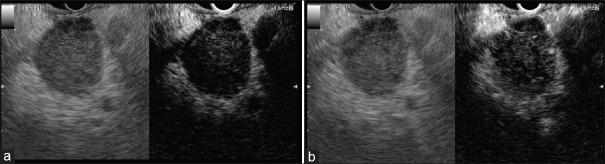

Contrast harmonic endoscopic ultrasonography (CH-EUS) is a new technique which allows the dynamic study of the microvascularization of a target tissue. Its application is validated for the diagnosis of pancreatic adenocarcinoma but remains unclear for other solid pancreatic tumors (neuroendocrine tumors [NETs], autoimmune pancreatitis [AIP], metastases). The purpose of this review is to outline the potential role of the CH-EUS in these indications. NETs are typically iso/hyperenhanced at CH-EUS, and a heterogeneous enhancement seems a good predictor of malignancy in neuroendocrine pancreatic tumor. AIP is often iso/hyperenhanced at CH-EUS. Quantitative analysis of time-intensity parameters is promising for the distinction between pancreatic adenocarcinoma and AIP. The appearance of pancreatic metastases at CH-EUS is various depending on the origin of the primary tumor. Data from the literature remain to this day weak to determine the role of the CH-EUS in the management of rare solid tumor of the pancreas (NETs, AIP, and metastases). Specific studies are expected to further clarify the impact of this procedure in this field.

对比谐波内镜超声检查(CH-EUS)是一种可对目标组织微血管化进行动态研究的新技术。其在胰腺腺癌诊断中的应用已得到验证,但在其他胰腺实性肿瘤(神经内分泌肿瘤[NETs]、自身免疫性胰腺炎[AIP]、转移瘤)中的应用仍不明确。本综述的目的是概述CH-EUS在这些适应症中的潜在作用。NETs在CH-EUS检查时通常表现为等增强/高增强,而异质性增强似乎是胰腺神经内分泌肿瘤恶性程度的良好预测指标。AIP在CH-EUS检查时通常也表现为等增强/高增强。时间-强度参数的定量分析有望用于区分胰腺腺癌和AIP。CH-EUS检查时胰腺转移瘤的表现因原发肿瘤的来源而异。时至今日,文献数据仍不足以确定CH-EUS在胰腺罕见实性肿瘤(NETs、AIP和转移瘤)管理中的作用。预计将开展具体研究以进一步阐明该检查在这一领域的影响。